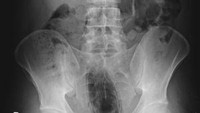

Pria berusia 56 di Nepal datang ke unit gawat darurat rumah sakit setelah memasukkan botol kaleng bekas ke dalam anusnya, 6 pekan sebelum ke dokter. Ia mengalami tinja keras, muntah, dan sakit perut. (Foto: International Journal of Surgery Case Reports)